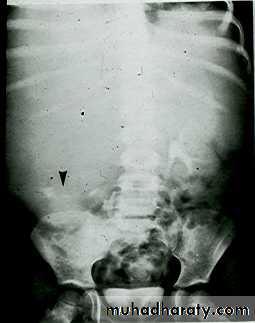

*Calcification is very common and important diagnostic findings. Very common in bladder ,less frequent in lower ureters ,but in advanced case involve the whole length of ureter .

*The appearance depends on degree of fullness of bladder ; thin linear opacity outlining bladder wall.

Empty bladder shows crowded linear opacities with calcified plaques.

Urinary Schistomiasis

• IVU: Early stage –cobble stone Later filling defects due to graneulomatos papilloma Carcinoma is important complication Ureters : dilated and tortuousIn early stage hydroureter and hydronephrosis + refluxSPACE OCCUPING LESION